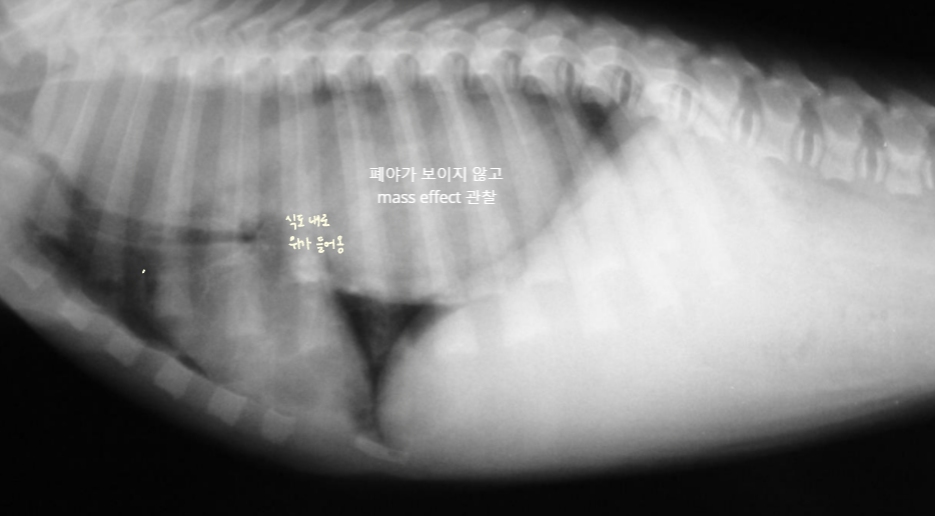

| Gastroesophageal intussusception (์์๋ ์ค์ฒฉ) |

|---|

| - ์์ ์ผ๋ถ๊ฐ ์๋๋ก ๋ง๋ ค๋ค์ด๊ฐ๋ ์๊ธ ์งํ - ์๋ ๋ด๋ก ์ ๋ด์ฉ๋ฌผ์ด๋ ์ ๋ง ์ฃผ๋ฆ ๋ฑ์ด ์ญ๋ฅ๋์ด ์ ๊ตฌ์กฐ๊ฐ ์๋ ๋ด์์ ๊ด์ฐฐ๋จ. ![]() |